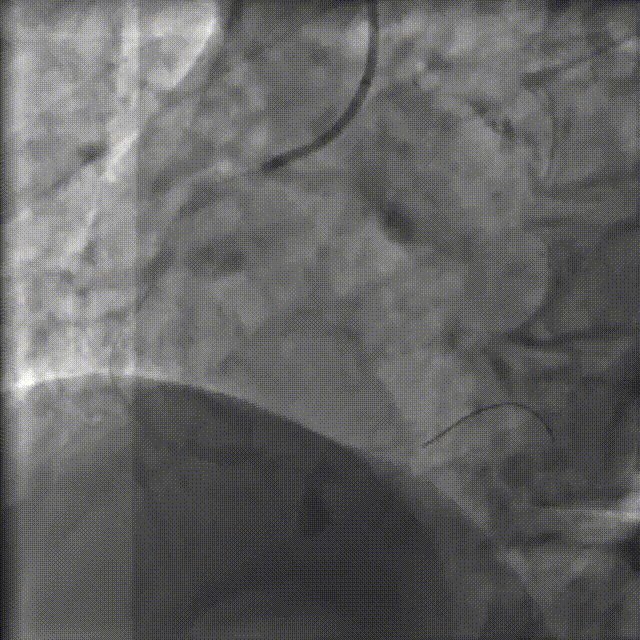

PCI过程-冲击波球囊PTCA

沿导丝送3.0×12mmGennWave冲击波球囊至RCA严重钙化病变处,充盈1:1比例造影剂盐水,以4atm低压扩张,每周期给予10秒、每秒1次血管内冲击波治疗后扩张至6atm,共进行8周期血管内冲击波治疗。

PCI过程-球囊PTCA

冲击波球囊完成后,进一步预处理,依次应用非顺应性球囊 2.75X15mm、非顺应性球囊 3.0X15mm、切割球囊 3.0X10mm等球囊反复由远及近进行扩张。